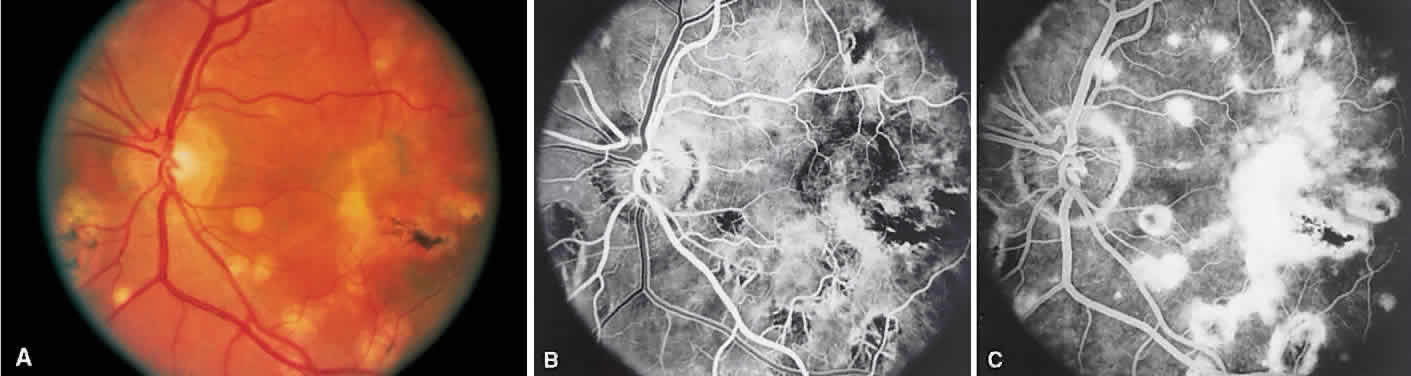

Birdshot retinochoroidopathy (also known as vitiliginous chorioretinitis) presents bilaterally, generally in middle-aged women, causing floaters and decreased vision, night blindness, and color blindness. Clinically, there are patches of postequatorial choroidal and retinal pigment epithelial depigmentation (Fig. 10A), vitreous cells, macular and disc edema, and venous sheathing. SRNV frequently is a late sequela. Often central vision may be preserved in at least one eye.

Fig. 10. Birdshot retinochoroidopathy. A. Multiple cream-color deep choroidal lesions. B. Fluorescein angiogram shows leakage of the optic disc and the retinal vasculature. C. Indocyanine green angiography showing areas of hypofluorescence that exceed those observed on fluorescein angiography.

On fluorescein angiography, retinal vessel staining, disc leakage, and cystoid macular edema are found (see Fig. 10B). There often is generalized hypofluorescence of the retinal vessels and increased circulation time.35,36 Surprisingly, the patches of depigmentation may appear normal on angiography, although there can be mild late hyperfluorescence.35,36 Posterior pole choroidal hyperfluorescent lesions that correspond to the areas of depigmentation and SRNV also can be seen.37

On ICG angiography (see Fig. 10C), early and late hypofluorescent patches, exceeding the clinically detectable lesions, with a choroidal vasotropic distribution and relative sparing of the peripapillary area and the central macula, are noted. These findings differentiate this condition from AMPPPE, multifocal choroiditis, and other granulomatous conditions such as sarcoidosis and sympathetic ophthalmia. Rarely, hyperfluorescent spots are noted in the late phases of the angiogram, which correspond ophthalmoscopically to retinal inflammation or obstructive changes.38